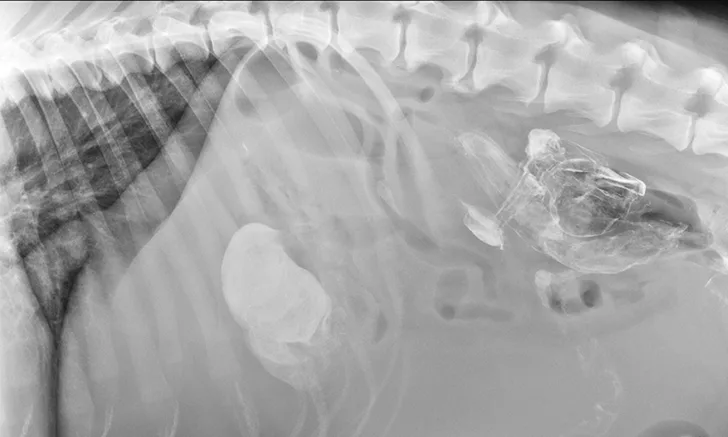

Treatment of the underlying disease in these conditions may relieve or reduce splenomegaly. In cases of splenic torsion (Figures 5 and 6), splenectomy is the recommended treatment, with approximately 90% of dogs surviving to discharge.19

Featured Image

FIGURE 5

Splenic torsion appears as a large soft-tissue opacity that displaces the GI tract caudally and peripherally (A). The splenic head is obscured caudal to the left margin of the stomach (B). The metallic opacity seen in the stomach and intestines is caused by recent barium administration.